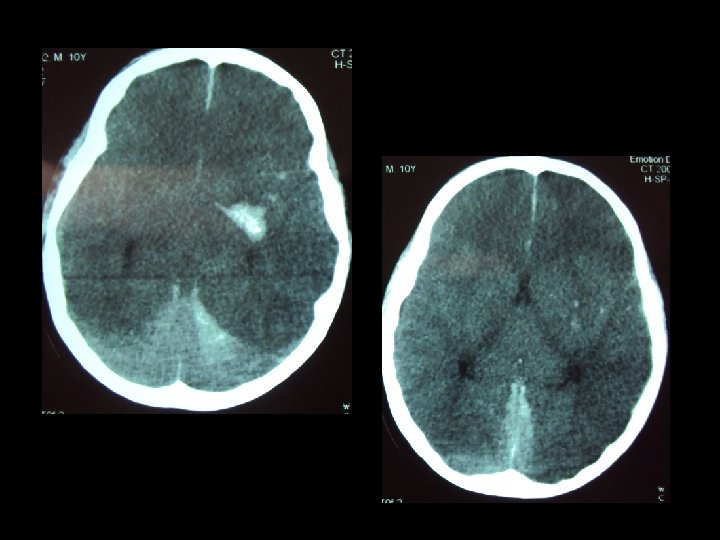

BỆNH NH N CTSN NẶNG PHẠM MẠNH K, NAM, 10 TUỔI TNGT TẠI VĨNH YÊN: 28/82008 BV TỈNH VĨNH PHÚC: HÔN MÊ, GCS 8 ĐIỂM KHÔNG LIỆT, VẾT THƯƠNG DA ĐẦU 10 CM KHÔNG CHỤP CLVT, CHUYỂN XUỐNG VIỆT ĐỨC: KHÔNG NỘI KHÍ QUẢN, KHÔNG TRUYỀN DỊCH, M 100, HA 80/40, THỞ KHÔNG ĐỀU (VĨNH YÊN-HÀ NỘI: 50 KM)

Khi h « hÊp & tuÇn hoµn æn ®Þnh Chôp c¾t líp vi tÝnh sä n·o Siªu ©m æ bông Chôp ngùc th¼ng Chôp cét sèng cæ th¼ng & nghiªng MỜI: 20 % CTSN NẶNG PHẢI MỔ -PTV THẦN KINH -BS CHUYÊN KHOA KHÁC NẾU CẦN

NGUYÊN NH N TĂNG ÁP LỰC NỘI SỌ Khèi m¸u tô chÌn Ðp khu tró N·o óng thñy Phï n·o ThiÕu m¸u n·o DËp n·o r¶i r¸c

TĂNG ÁP LỰC TRONG SỌ: RÕ RÀNG NẾU: TRI GIÁC XẤU DẦN, CLVT (MÁU TỤ LỚN, NÃO ÚNG THỦY) KHÔNG RÕ NẾU: -DẬP NÃO -PHÙ NÃO -MÁU TỤ NHỎ -THIẾU MÁU NÃO… CHẨN ĐOÁN TĂNG ÁP LỰC TRONG SỌ BẰNG CÁCH NÀO ?